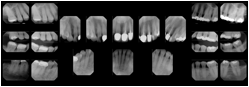

2. A patient requests cosmetic surgery to enhance their facial appearance. The case requires consultation between an orthodontist in New York and an oral surgeon in California. The cephalometric series of 2D projections constructed from a volumetric CT data set that is used for the discussion is arranged by a Structured Display for transfer between the two practitioners.

Cephalometric Series Structured Display

Figure OO-2. Cephalometric Series Structured Display